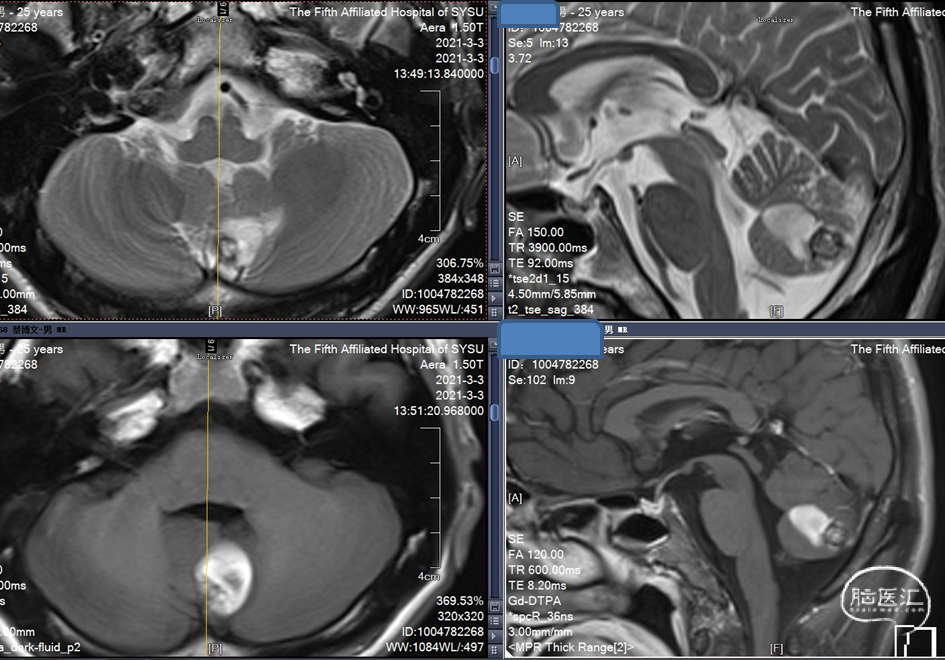

MRI 扫描:有边界,呈圆形。病灶在 T1 加权像呈等信号,在 T2 加权像或注射对比剂后呈高信号,病灶内有混杂低信号,病灶周围有环形低信号带。小型 (<1 cm) 以及非出血性海绵状血管瘤,磁敏感加权成像(SWI)的检出率更高。

脑干海绵状血管瘤是一种多发的海绵状血管瘤。患者于2017年发现海绵状血管瘤,2018年由于反复出血做手术,手术效果好。2020年11月,患者头痛并有出血症状。2020年12月再次出血,第二次手术。复查CT,情况良好。

此次手术采用内镜。内镜的优点:创口小,体位要求比显微镜低,操作空间大。缺点是稳定性不够好。